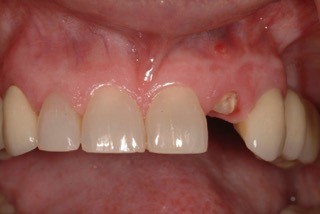

Both Caroline’s and Karen’s lateral incisors were removed, and immediate implants were placed. Although the implant surgeons were different, they were both long-time members of my interdisciplinary team and had significant implant placement experience. Both implants were torqued to 50 Ncm at the time of placement. Provisionals were then placed by me that same day.

Following four months of healing, Karen was appointed in my office for the final restoration of the implant. The provisional was removed, without anesthesia, and the implant impression post was secured to the newly healed implant. The restorative process was uneventful, and a ceramic restoration and gold post were placed.

Alternatively, Caroline was scheduled for her implant restorative process. Again, no anesthesia was utilized. The retaining screw was loosened, and the provisional was removed. Upon tightening the impression post to the implant, Caroline winced with pain! The implant was not integrated! Why?

The failed implant was removed. Following the healing of the site, a second implant was placed. Again, a provisional was placed on the new implant at the time of placement. Maintenance and care instructions were provided. This implant healed uneventfully four months before final restoration. Caroline was delighted with this result.